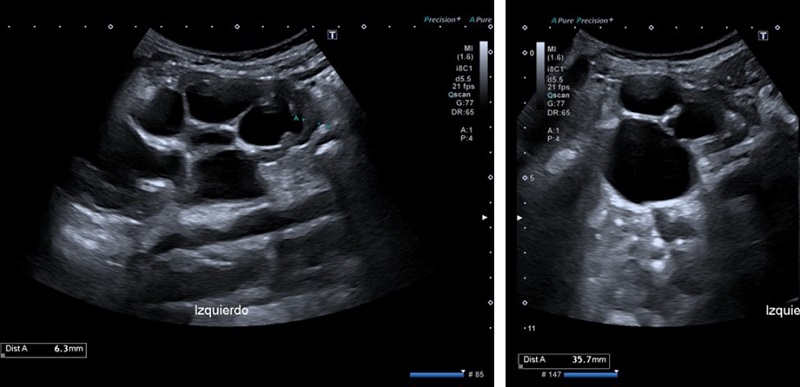

En ecografía abdominal se objetiva hidronefrosis renal izquierda grado III-IV y adelgazamiento cortical (Fig. 1).

| Figura 1. Ecografía de riñón izquierdo. Imagen izda.: marcada disminución de la cortical, grosor máximo de 6,3 mm. Imagen dcha.: diámetro longitudinal de 101,9 mm, gran dilatación pielocalicial con diámetro AP de pelvis de 35,7 mm |